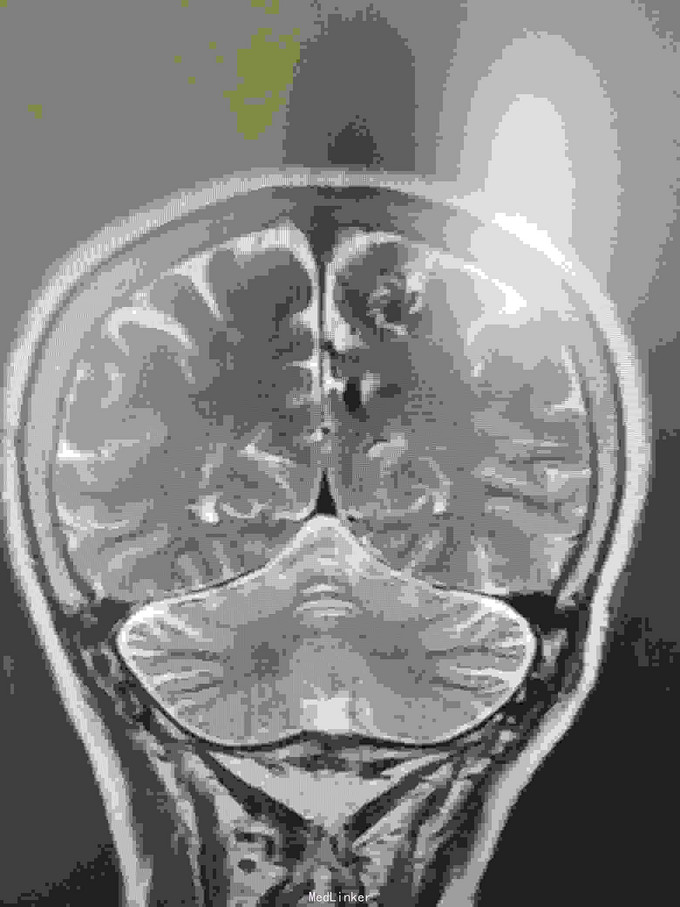

女性,65岁。入院前半年查出AvM,半年后出血入院。

左枕顶区AVM。 左大脑后及左大脑前供血,深部静脉回流。